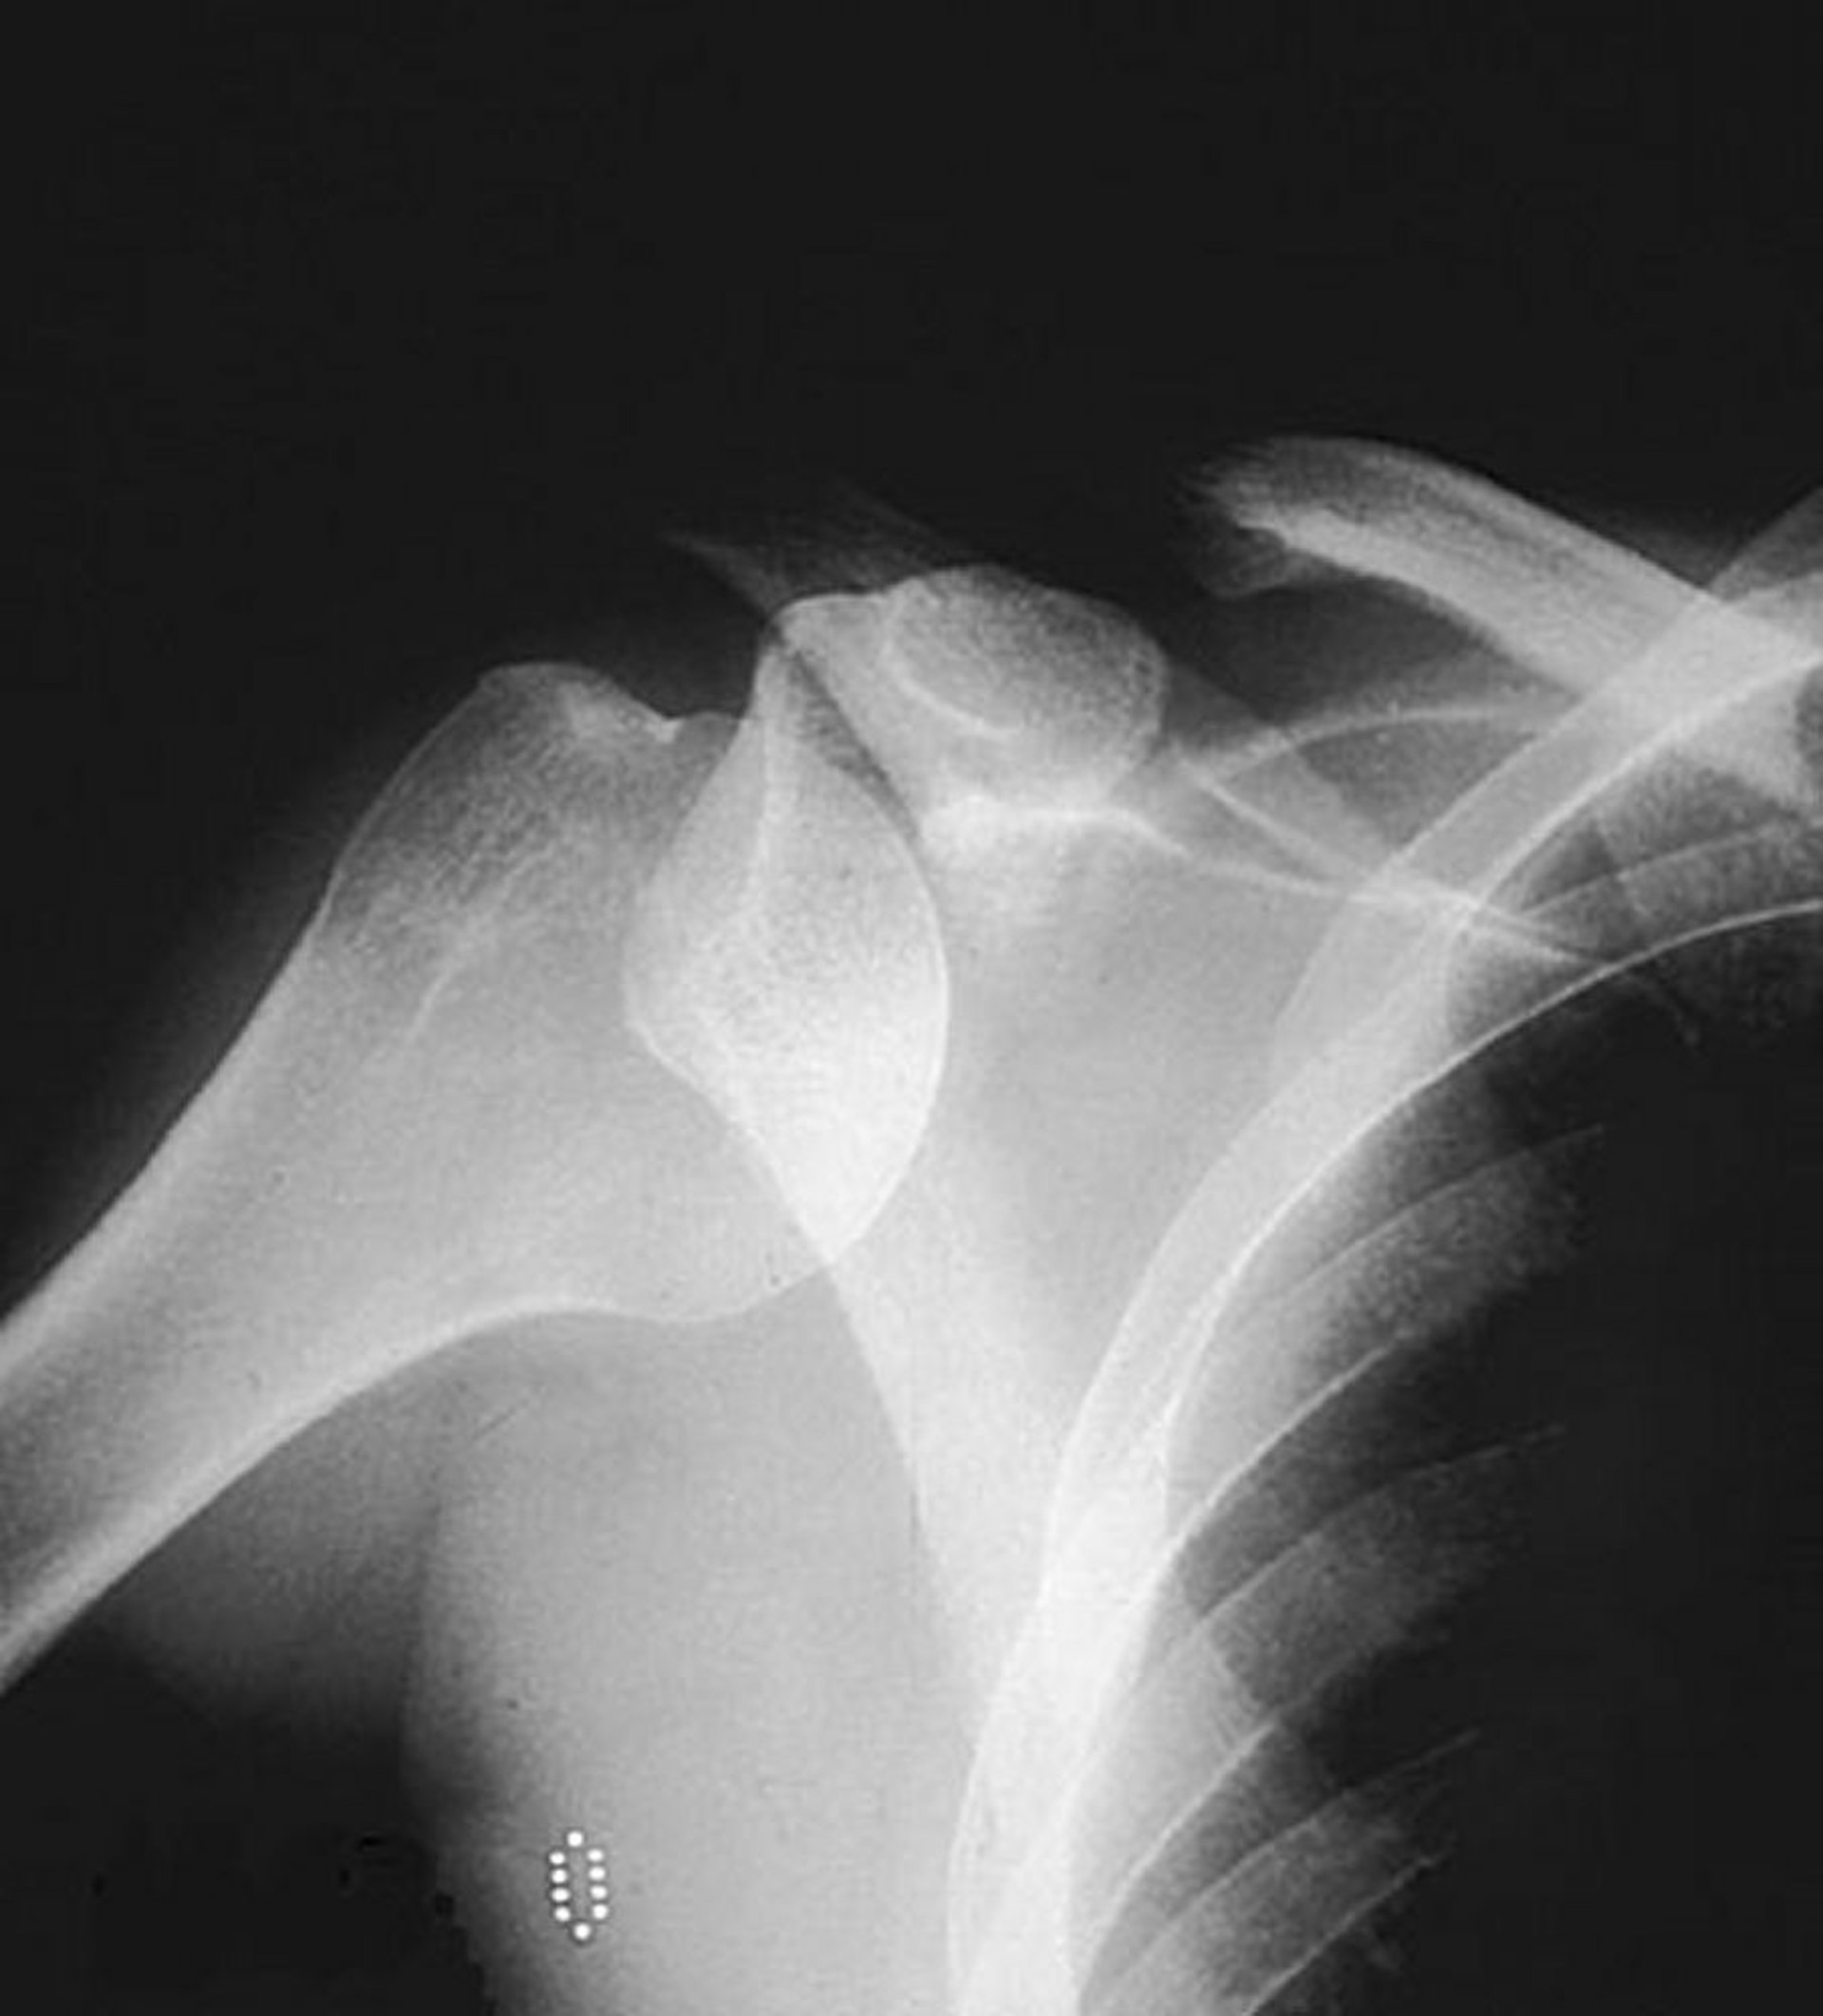

Передний суставно-плечевой вывих (плечевого сустава)

На переднезаднем обычном рентгеновском снимке показана головка плечевой кости, находящаяся вне ее обычного расположения в пределах гленоидной ямки, что свидетельствует о переднем вывихе.